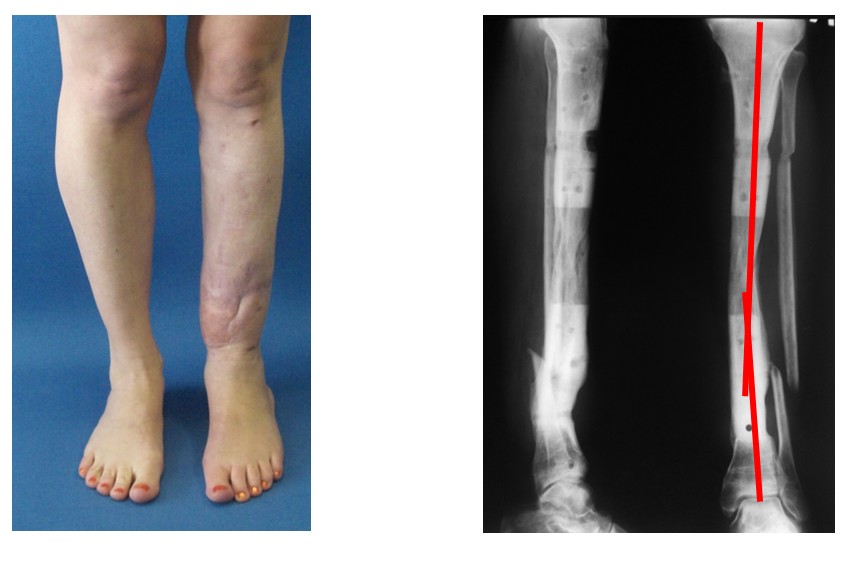

Пациентка с посттравматической деформацией большеберцовой кости